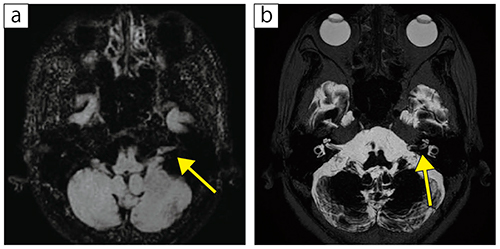

■症例1:左聴神経腫瘍

70歳代,女性。めまい感を主訴に同クリニック受診。聴力低下の自覚はない。MR画像で左内耳道に腫瘍性病変を認める。

a:3D-FLAIR(FatSat),MPR(AX),TR/TE=5000/138,FA=90°,スライス厚:1.2mm,撮像時間:4分46秒,MPR処理:スライス厚3.0mm,スライス間隔3.0mm

b:3D-isoFSE,MIP(AX),TR/TE=3000/408,FA=90°,スライス厚:1.0mm,撮像時間:2分4秒,MIP処理:スライス厚8.0mm,スライス間隔1.0mm